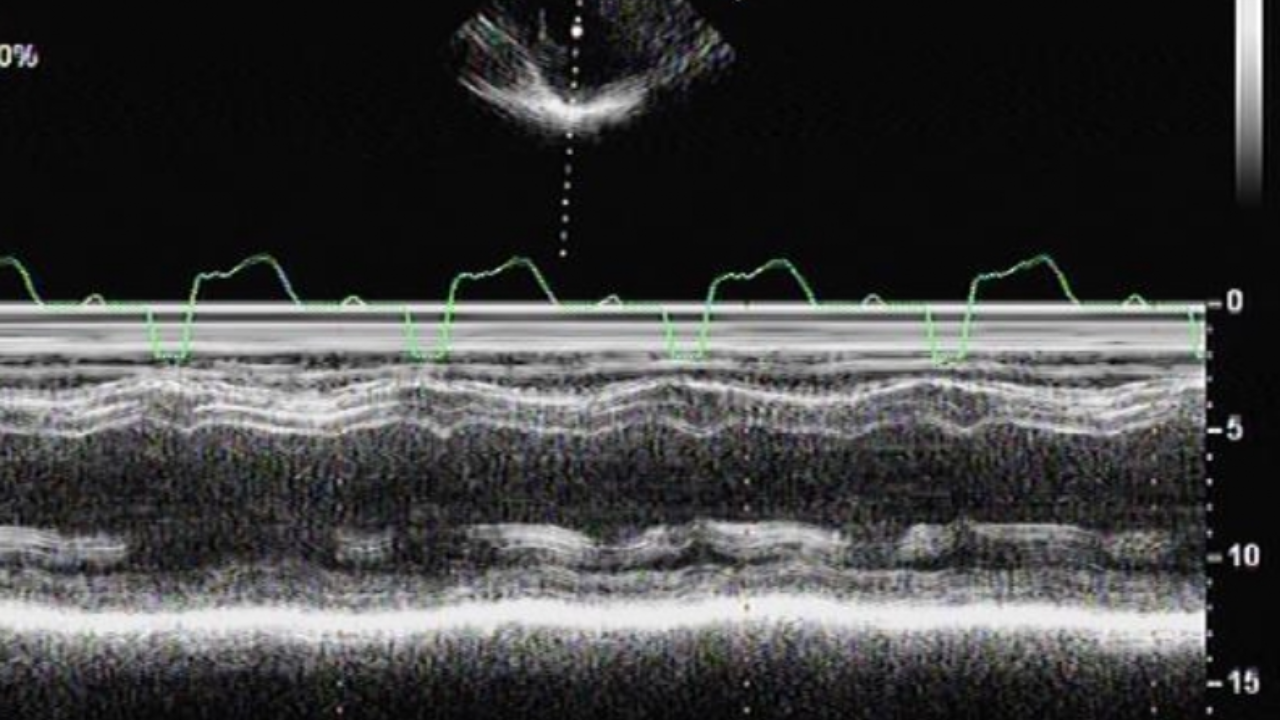

先看个跳跳鱼:

心超动图1: